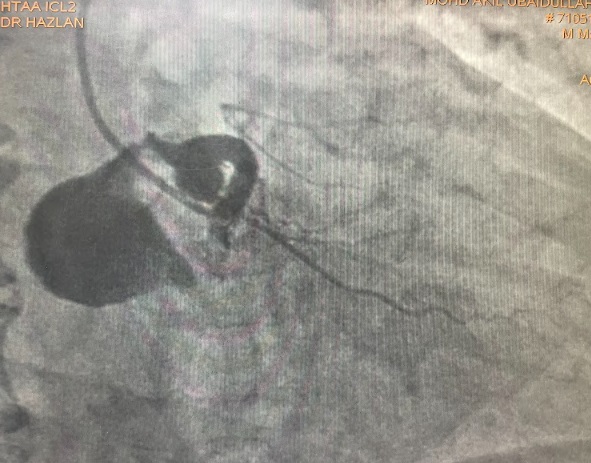

Coronary angiography showed a dominant RCA with a large proximal aneurysm measuring 4.5 ¡¿ 17 mm, with in-stent restenosis proximal to the aneurysm. Mid-to-distal RCA was ectatic. The LM, LAD, and LCx were also mildly ectatic but without significant stenoses. These findings were consistent with a giant RCA aneurysm, likely related to prior stent implantation.